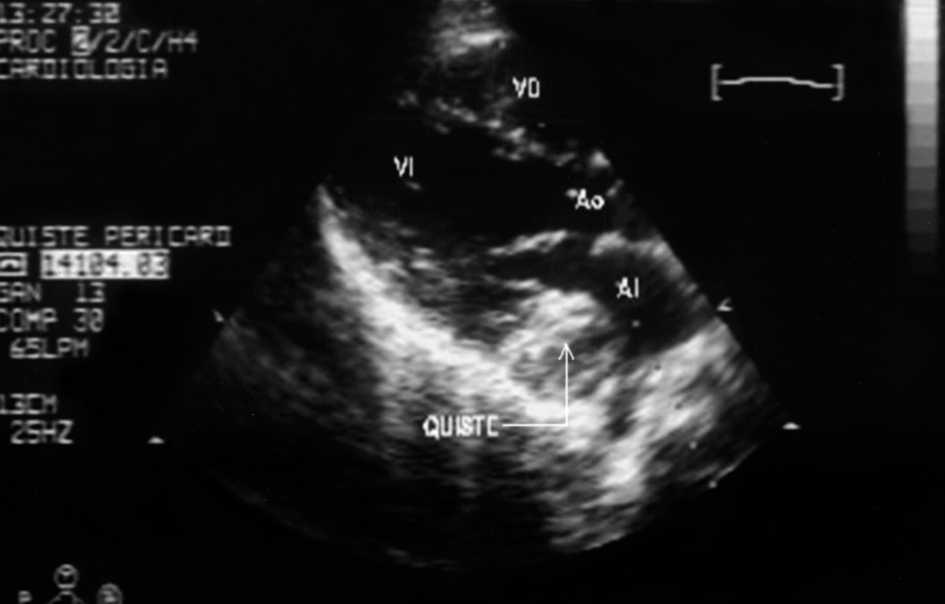

Se presenta el caso de un varón de 12 años de edad, de origen búlgaro, intervenido de hidatidosis cardíaca primaria en surco auriculoventricular derecho hacía 3 años, remitido a nuestro servicio por sospecha de recidiva. Se encontraba asintomático cardiológicamente, y en la exploración únicamente presentaba roce pericárdico en ápex. El electrocardiograma objetivó un ritmo sinusal con bloqueo incompleto de rama derecha y la radiografía de tórax mostraba leve cardiomegalia. El ecocardiograma transtorácico evidenció una tumoración sólida capsulada de 3 x 3 cm de diámetro de contenido heterogéneo que protruía en la aurícula izquierda sin provocar un gradiente hemodinámico significativo (figs. 1 y 2). Se descartó la presencia de formaciones quísticas en otros órganos mediante técnicas de imagen. En la analítica destacaba una discreta eosinofilia, resto de las series, velocidad de sedimentación globular (VSG) y bioquímica hepática normales. La serología de hidatidosis fue positiva (títulos 1/1.280).

Figura 2.Eco transtorácico proyección cuatro cámaras con Doppler-color: protrusión de la misma masa en el interior de la aurícula izquierda, sin causar compromiso hemodinámico. AI: aurícula izquierda; AD: aurícula derecha; VD: ventrículo derecho; VI: ventrículo izquierdo.